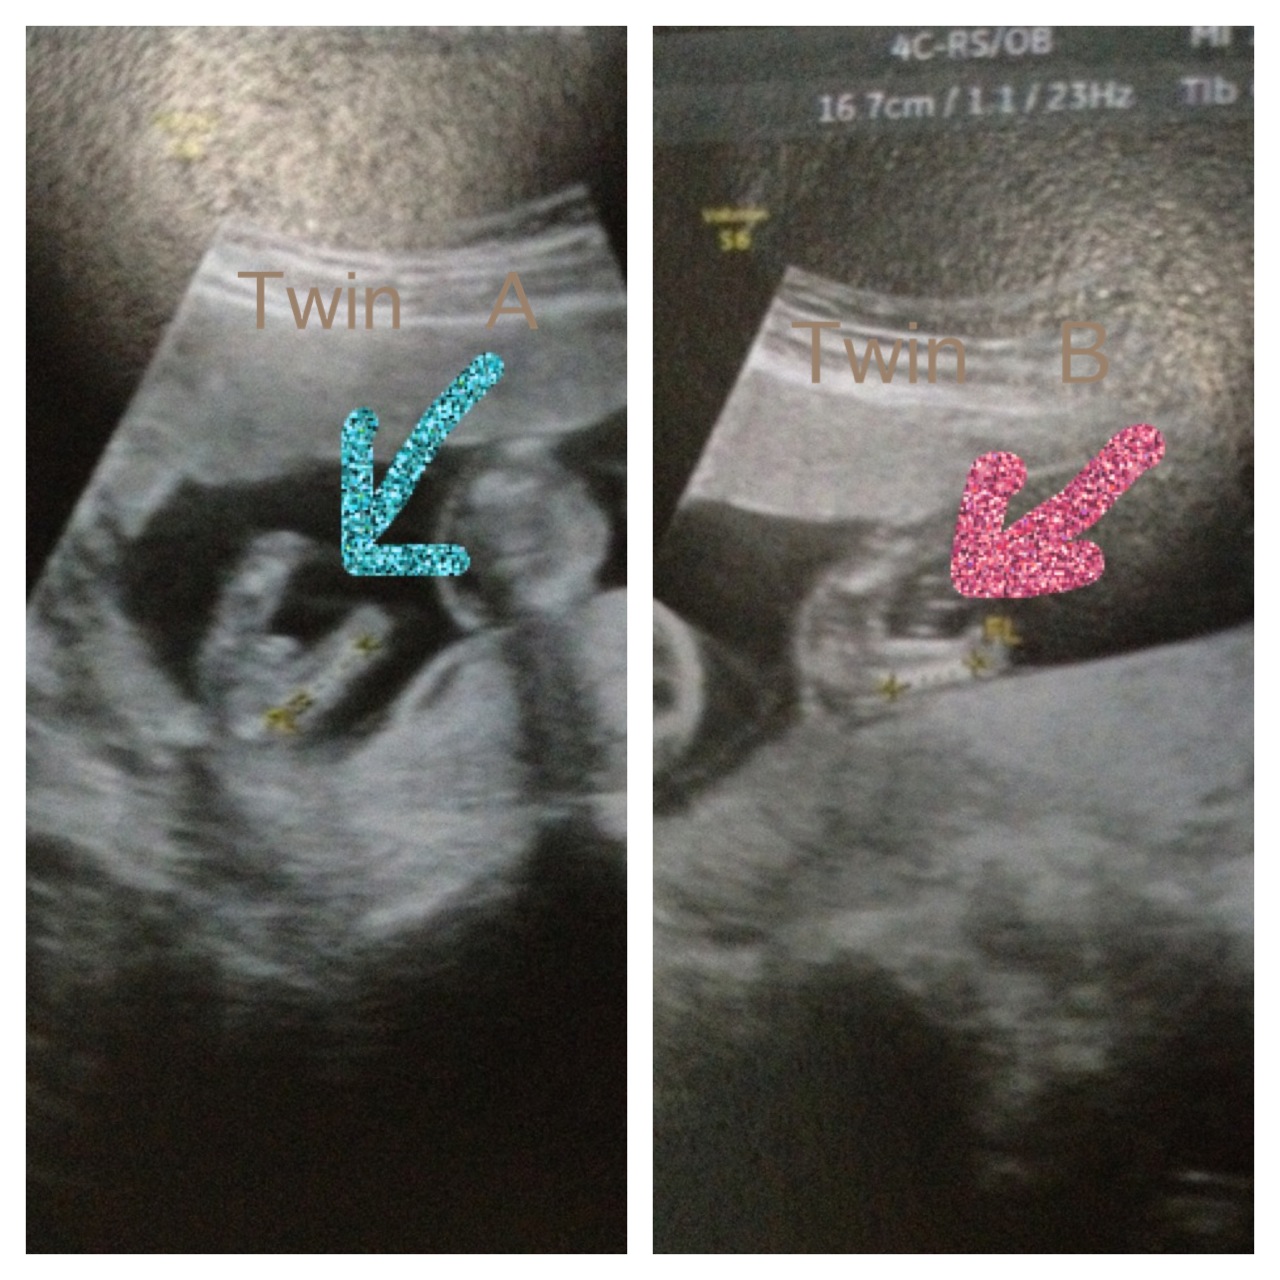

:::รบกวนช่วยดูเพศน้องแฝดทีค่า::::

น้องแฝดคนละใบค่ะ ใครพอดูออกบ้างคะ หมอบอกมาค่ะแต่หมอบอกแค่90% ค่ะ ตอนนี้15วีคค่ะ

เลยจะรบกวนเพื่อนๆมาช่วยฟันเฟิร์มอีกทีค่า